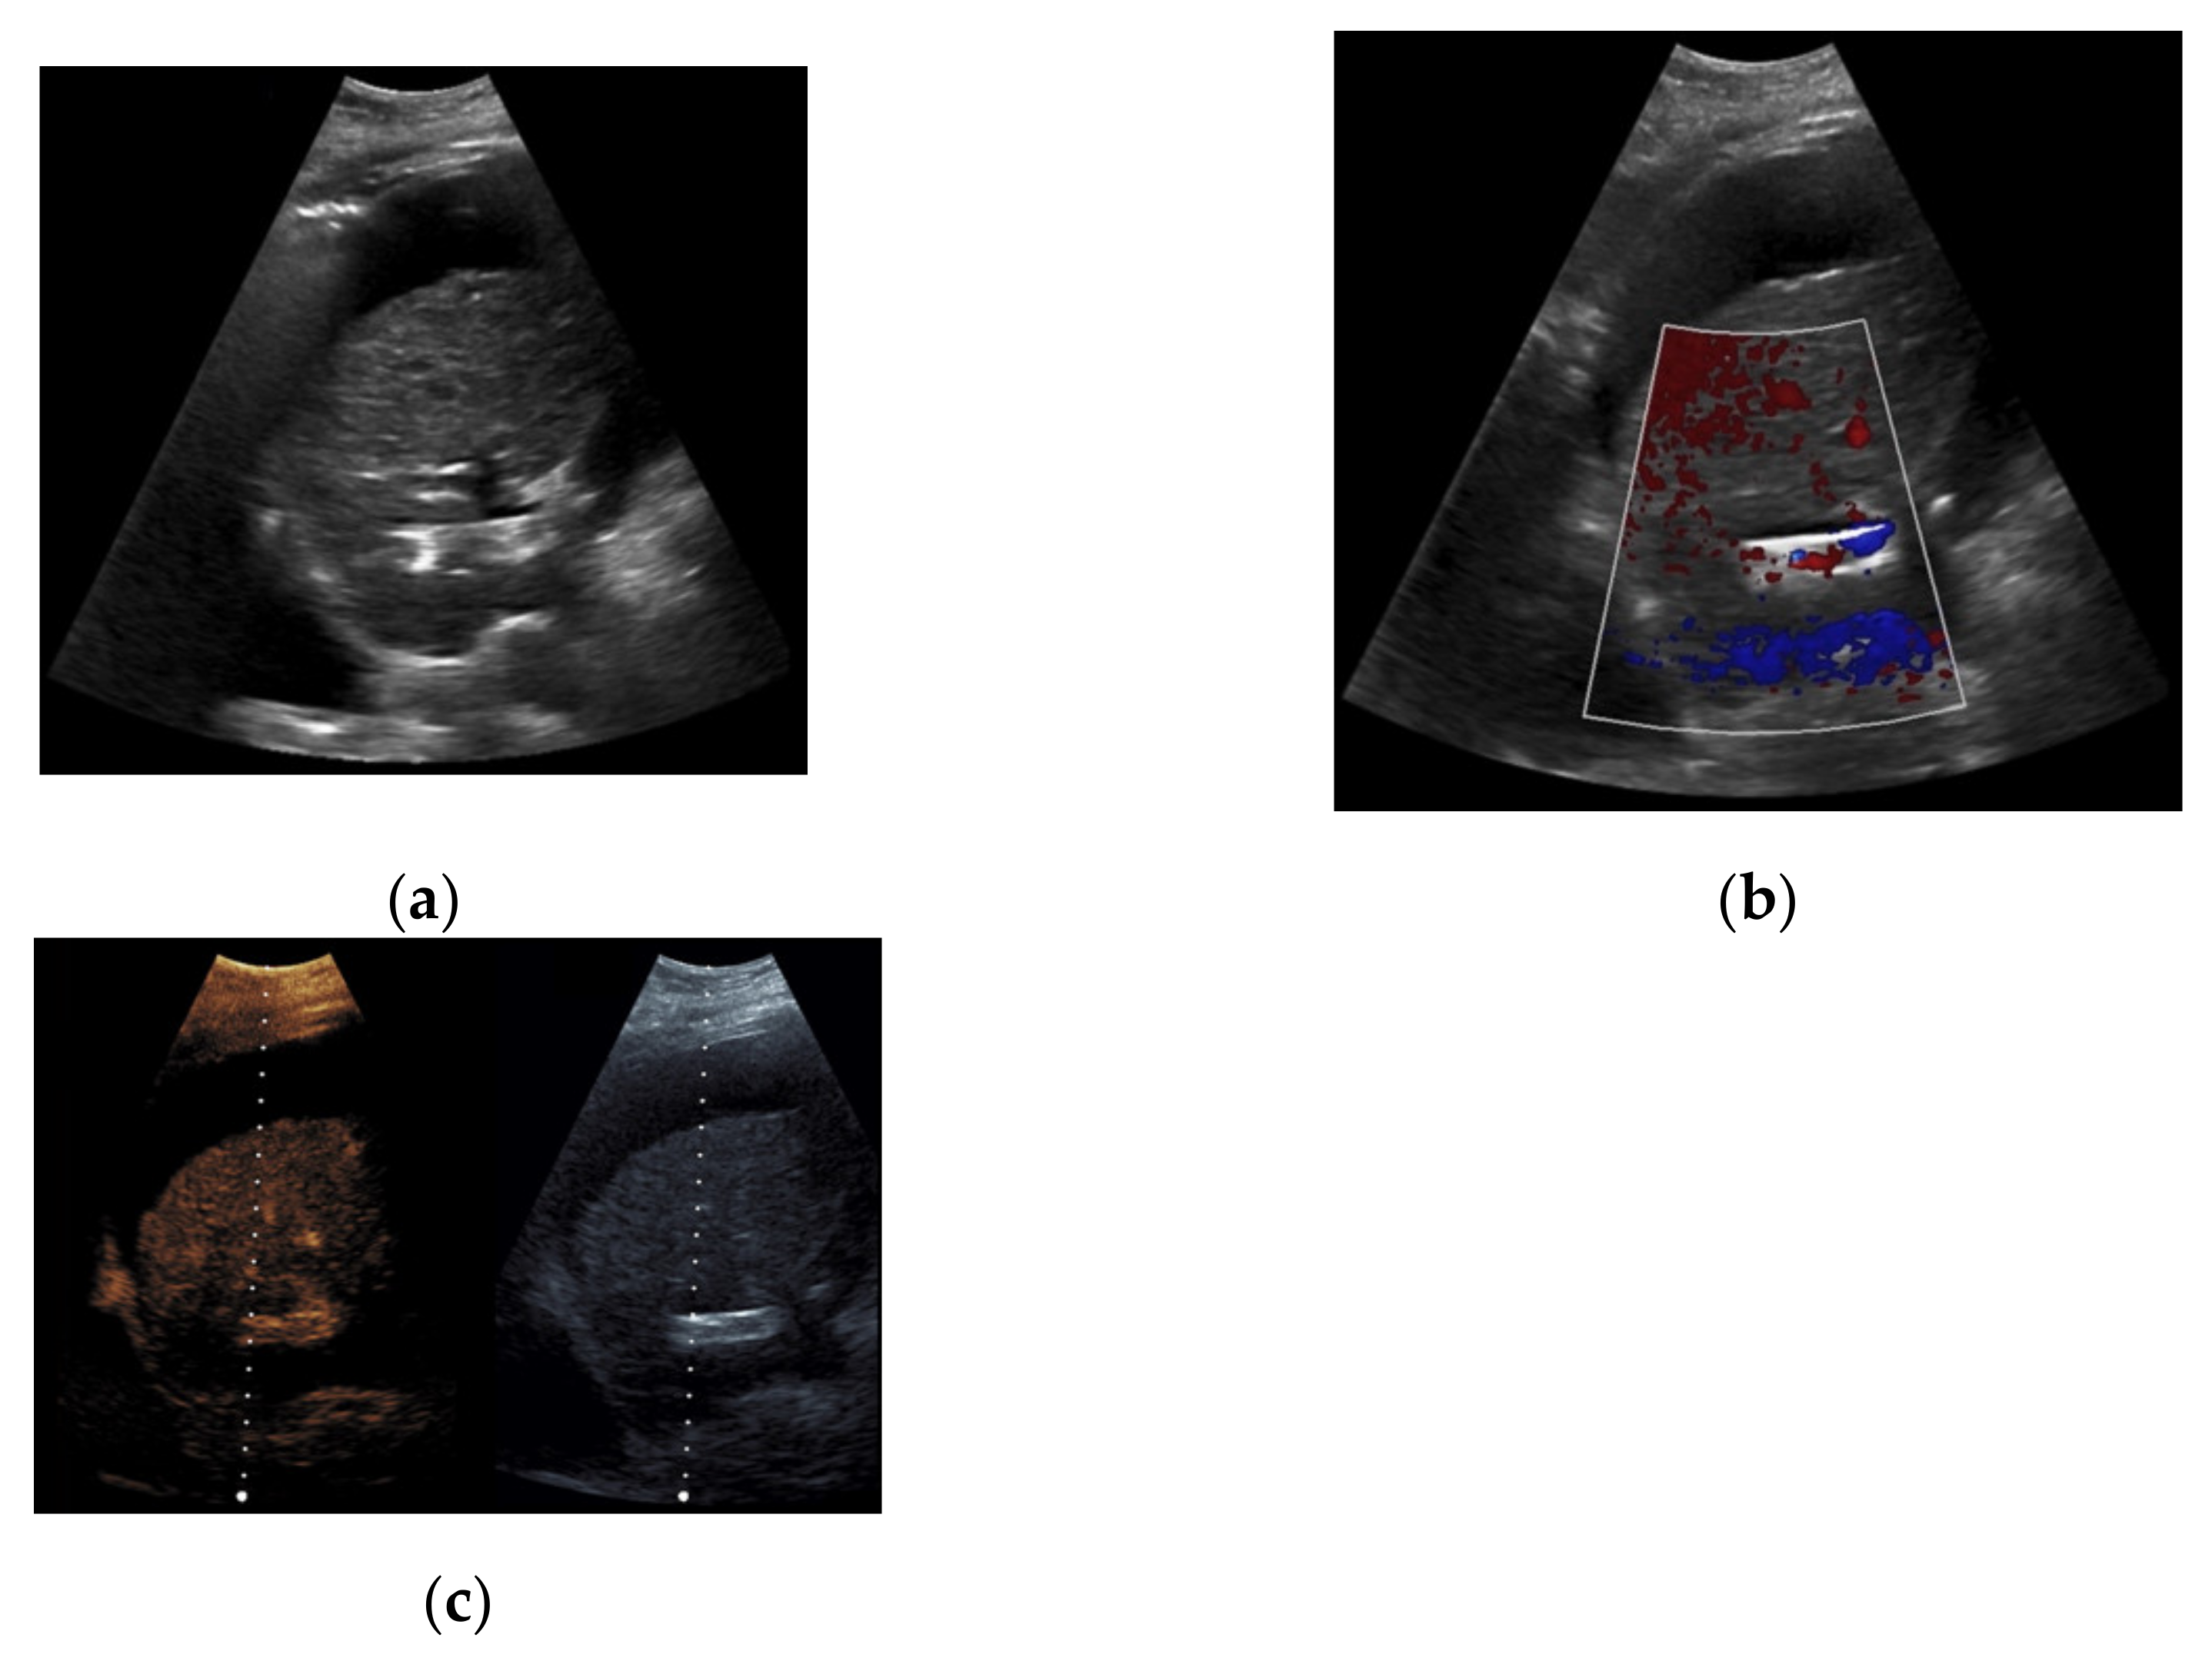

Based on initial findings from CDUS, 67% (n = 71) of the patients showed normal perfusion within the TIPS (Figure 1). 18% (n = 19) of the cases presented stent occlusion (Figure 2) while 6% of the patients (n = 6) had partial occluding stent thrombosis (Figure 3). The TIPS perfusion in five patients was only partially assessable, while in two patients an examination was not feasible due to extensive meteorism. The patients listed under “others” showed postoperative entrapped air between the wall of the vessel and the stent (n = 2) while one patient had two TIPS, one occluded and one with a normally detectable blood flow (Table 1).

When taking a closer look at the results of the CEUS examinations, 70.8% (n = 75) of the patients showed regular stent perfusion (Figure 4), 17.9% (n = 19) of the patients featured TIPS occlusion (Figure 5) while 6.6% (n = 7) patients had stent thrombosis (Figure 6). In contrast to the results from CDUS, there were no patients with only partial accessibility of the TIPS during CEUS, while the two patients with meteorism also were not assessable during CEUS. The three patients categorized in “others” showed simultaneous findings between CDUS and CEUS (Table 2).

Figure 1. 65-year-old patient with regular visualization of the transjugular intrahepatic portosystemic shunt (TIPS) during B-mode (a) and adequate visualization of the TIPS in Color Doppler ultrasound (b) with inconspicuous flow and flow velocity (c).

Figure 2. 57-year-old female patient with occluded transjugular intrahepatic portosystemic shunt in B-mode (a) and consecutive absent flow signal in Color Doppler ultrasound (b).

Figure 3. 44-year-old female patient with inhomogeneous flow signal on Color Doppler ultrasound as a sign of stent thrombosis.